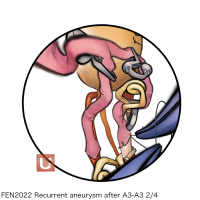

FEN2022シリーズ